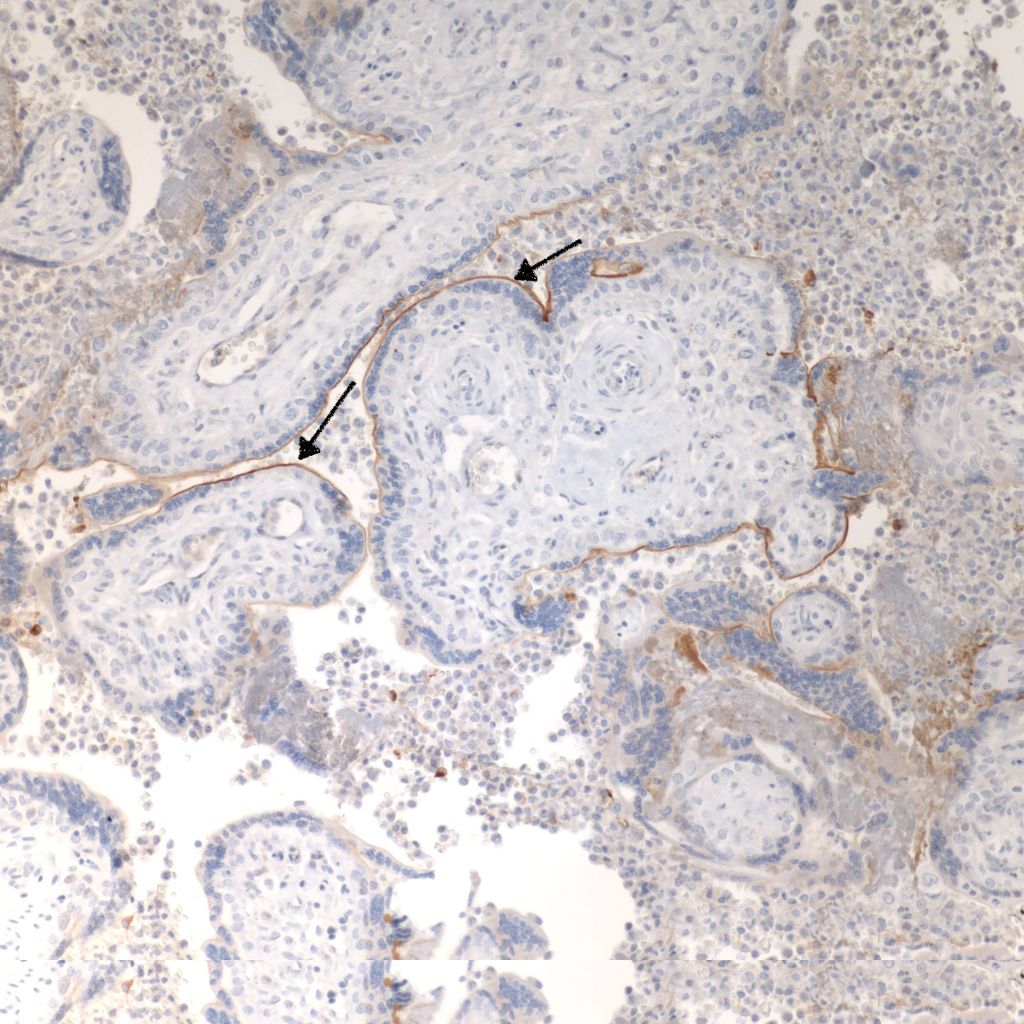

CD68 or alkaline phosphatase: to confirm that the intervillous cells are monocytes, but is not required for meeting the diagnostic criteria

C4d: to show evidence of complement fixation on the microvillous surface of the syncytiotrophoblast. While further study is needed, the subclassification of intervillous monocyte accumulations into those with and without complement fixation and the subclassification of villitis of unknown aetiology with intervillous monocytes into those with and without complement fixation may prove to be a useful distinction.

C4d: One study of CHIV compared 3 histologic groups of placentas demonstrating intervillous histiocytes: Few intervillous monocytes, massive intervillous monocytes, and intervillous monocytes associated with villitis of unknown aetiology18. Each group was further divided into subcategories based on the extent of c4d immunostaining of the microvillous surface of the syncytiotrophoblast. The outcome variables were fetal death or growth restriction. In the analysis, without a formal ROC study, it appeared that staining less than 25% of the villous surface was a natural cut off point from greater than 25%. As can be seen in the Table 1 of the raw data, that with rare exceptions, all the cases with less than 25% of c4d trophoblast staining, and often without any staining, were either associated with few intervillous monocytes, or with villitis. Fetal death or growth restriction was almost always associated with more than 25% of the villous surface stained with c4d. The lack of statistical significance in the comparisons is likely due to small sample size.

1. Direct evidence of Immune injury in intervillositis: The accumulation of monocytes in the intervillous space is the dominate evidence of an immune origin of intervillositis. The accumulation is likely due to both a chemotactic response and increase in either a cell adhesion molecular on the monocyte surfaces or possibly a secondary ligand that is linking monocyte surface molecules. One piece of evidence of an immunologic injury is the staining of the microvillous surface of syncytiotrophoblast by c4d, a stable complement product used routinely in pathology laboratories in identify antibody-mediated rejection in biopsies of transplanted organs. T-cells have been identified as a minority population in intervillostitis, but a regulatory role cannot be excluded. There is evidence in one study of in vitro T-cell activation.